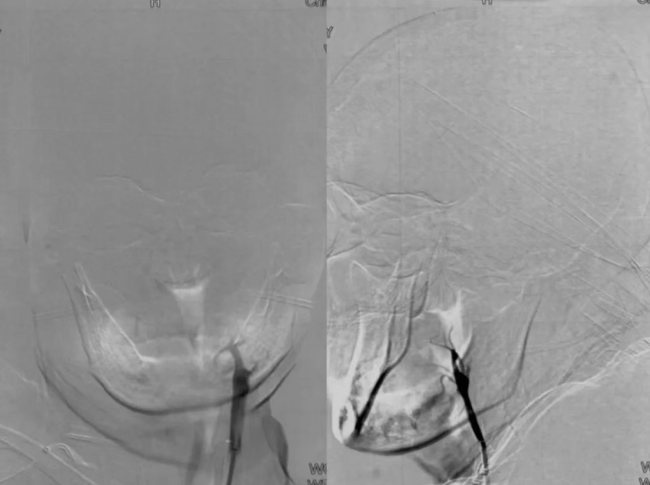

由于大血管闭塞病情危急,卒中团队立即启动绿色通道,行全脑血管造影(DSA)检查,证实右侧颈内动脉末端闭塞。经与家属充分沟通后,神经介入团队行机械取栓术,成功取出数枚血栓,术后血管恢复通畅。患者意识逐渐转清,肢体功能明显改善,经观察治疗后出院。